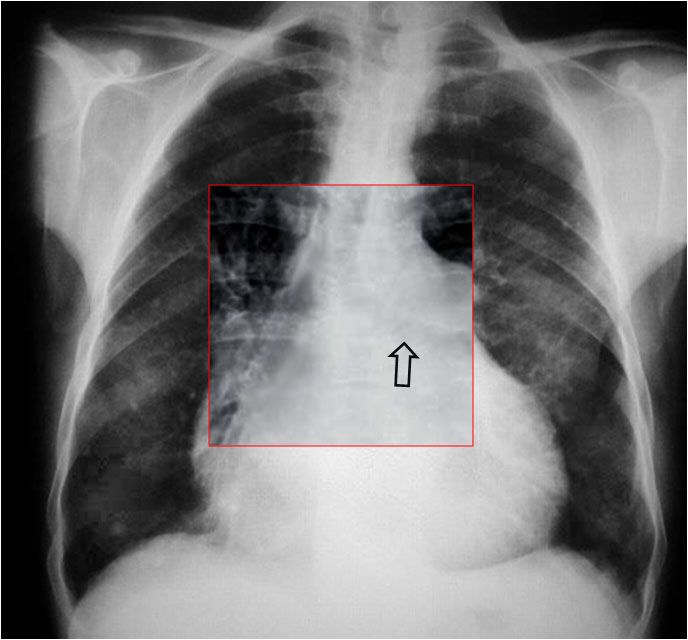

La irregularidad, abombamiento o borramiento del arco aórtico en la radiografía de tórax en bipedestación o en decúbito supino, en un paciente con traumatismo torácico, obliga a descartar rotura aórtica como causa de dicha alteración. La flecha muestra el contorno aórtico anómalo. Además, hay un aumento de densidad en el hemitórax izquierdo correspondiente a derrame pleural –hemotórax en este caso-, que refuerza la sospecha de rotura aórtica.